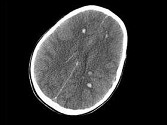

- 单项选择题男,25岁, 头颅外伤,昏迷, 意识丧失,结合CT图像, 最可能的诊断是 ( )

A、结节性硬化病

B、脑剪切伤

C、脑囊虫病

D、脑实质钙化灶

E、脑转移瘤